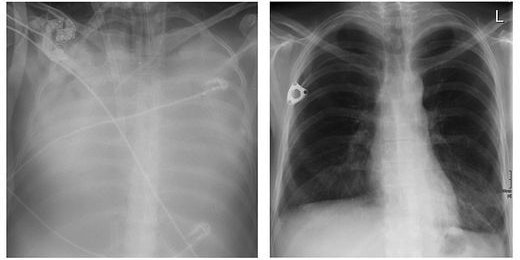

Sabines Lunge mit Covid-19 (l.); ihre neue Lunge (r.)